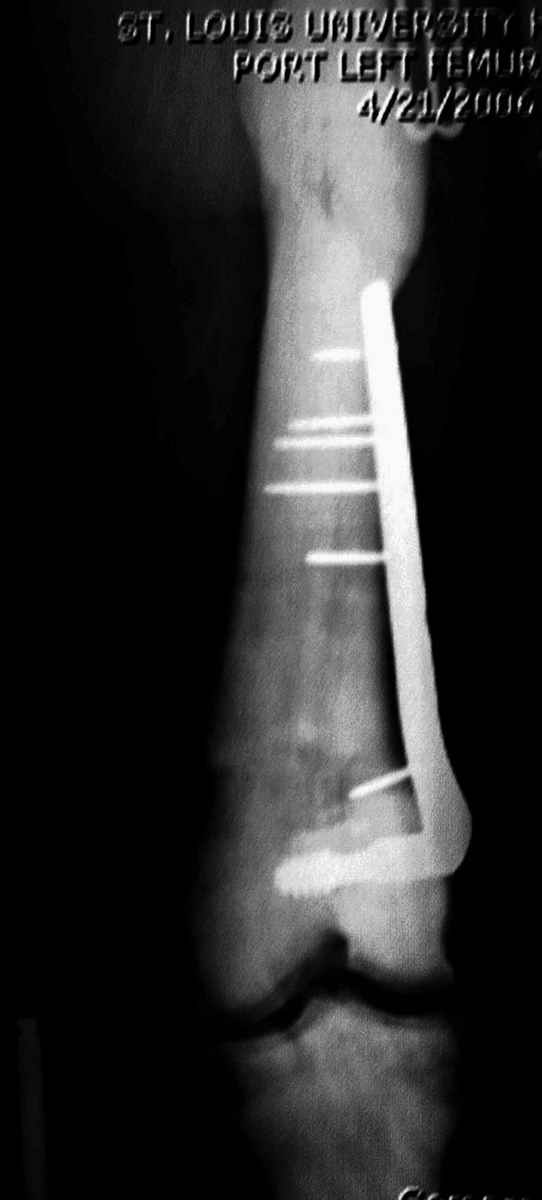

“При лечении переломов у больных с остеопетрозом (в прошлом году был случай) необходимо быть готовым к длительным операциям из-за трудности

обработки традиционными методами "мраморной" кости, иметь в наличие достаточное количество свежих острых инстументов и персонала при необходимости замены (были случаи отстрочки операции на следующий день из-за физической усталости персонала), и надо избежать особо трудоемких операции как интрамедуллярное сверление”.

Не являюсь специалистом по костной патологии, но мне кажется, на ренгенограмме множественные мета-диафизарные образования напоминяющее змееподобных извилистых линии и периостеальные ламинирование очень напоминяет картину остеонекроза (инфаркта) костей, возможно связано с длительным применением стероидов.

При предоставлении дополнительных информации, сканнирования, МРТ и лабараторных данных можно уточнить предварительный диагноз, пока склонен к обширному костному инфаркту, и таких больных рекомендуем лечить сиптоматически.

слайды из прошлегодного случая.